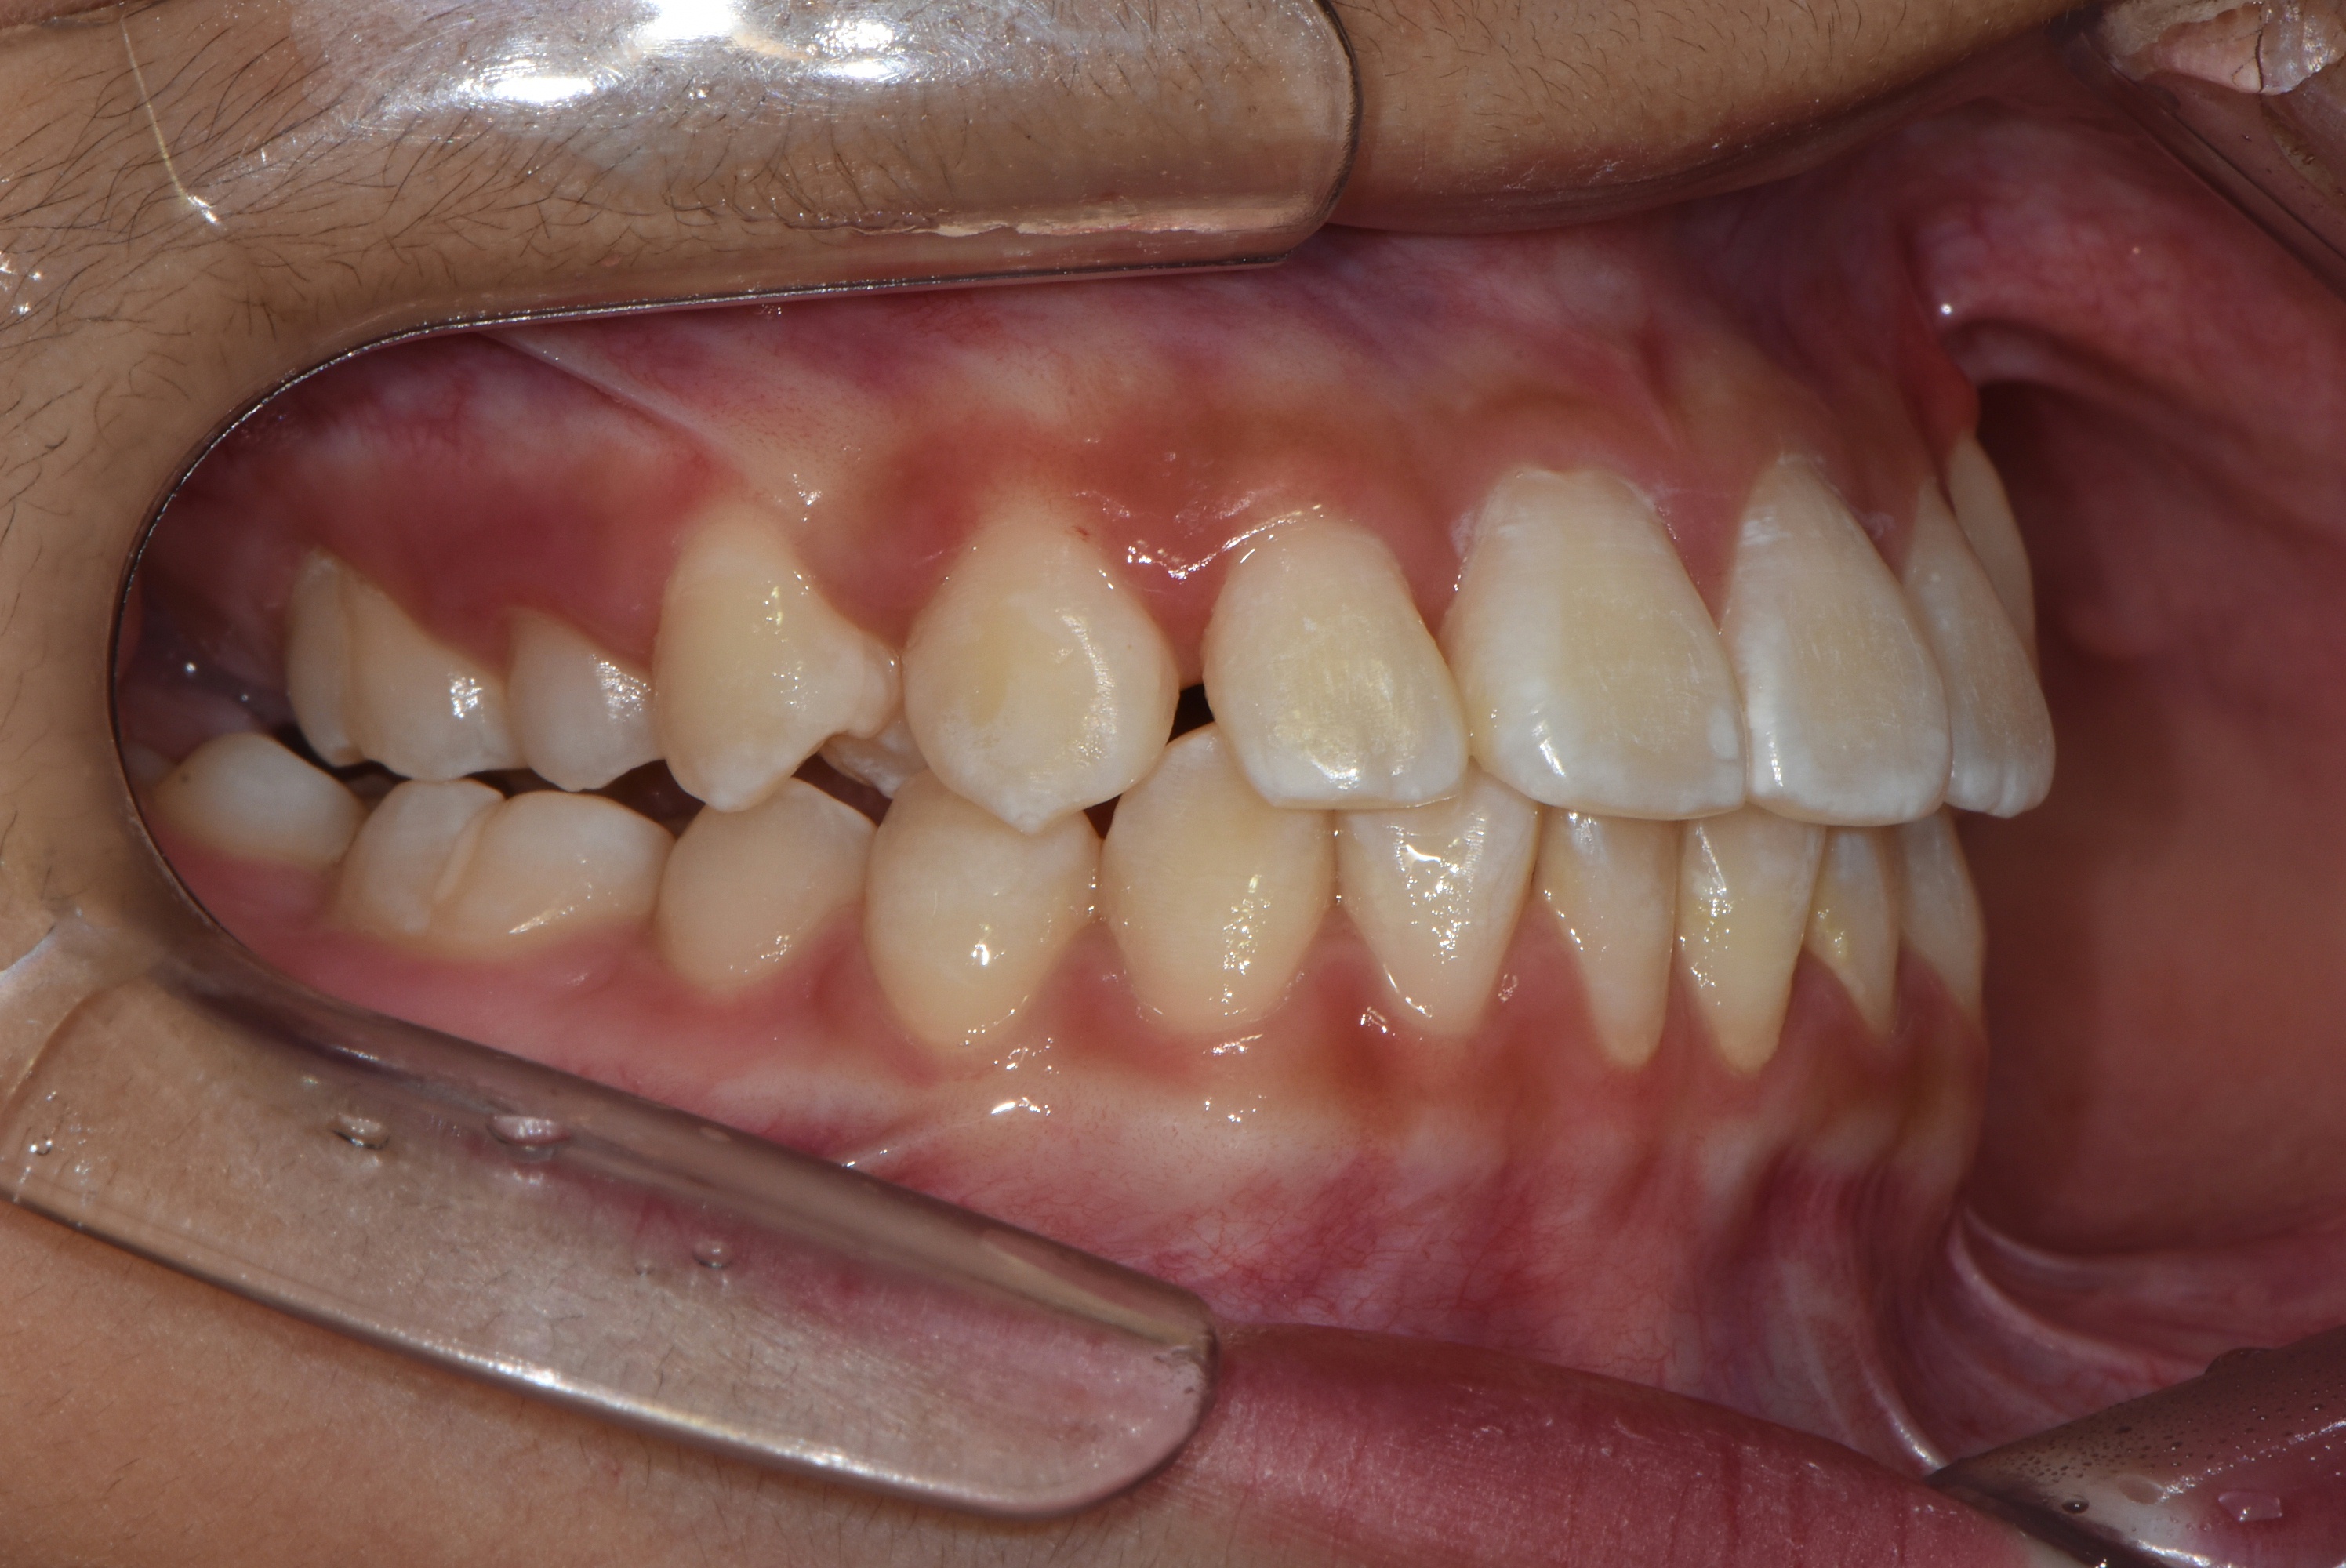

치료 전 사진입니다.